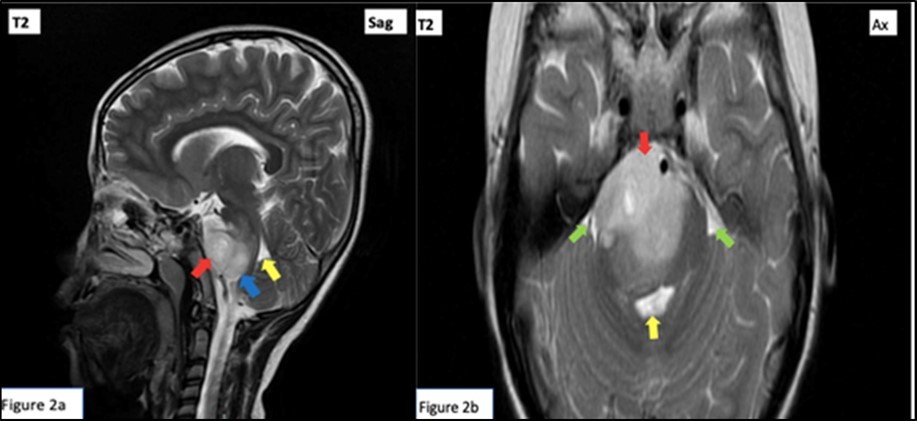

Cranial MRI with contrast was done, revealing a right pontine mass with features of glioma typical of a diffuse intrinsic type exhibiting T1 hypointensities, T2 hyperintensities involving majority of the pons with associated signal changes.4Hence, patient was diagnosed with Raymond Syndrome probably secondary to a presumed pontine glioma, Right. Patient was referred for evaluation and co-management with Neurosurgery and Pediatric Neurology services. Patient subsequently underwent radiotherapy.

Red arrow: Peripherally enhancing 2.6 x 4.1 x 2.8 cm lobulated mass centered on the right tegmentum of the pons, exhibiting hyperintensity (and hypointensity in T1 weighted images, not shown). Mass renders the pons enlarged and displaces the rest of the pontine parenchyma peripherally. Green arrow: Effacement of bilateral cerebellopontine angle. Yellow arrow: Mild compression on the 4th ventricle. Blue arrow: Small similar looking lesions at medulla oblongata. (Figure 1, Figure 2)

Figure 2.T2 Weighted cranial magnetic resonance imaging sagittal (a) and axial (b) cuts.

T2 Weighted cranial magnetic resonance imaging sagittal (a) and axial (b) cuts.